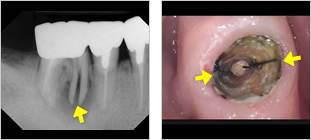

- 3位破折(はせつ)

- 歯の根が折れていたり、割れている状態

- 割れている部分から汚れが入り込んで歯周病のように骨がなくなる

- 歯茎が腫れたり、膿が出てきたりする

- 噛むと痛い

自覚症状がなく経過する場合もある。